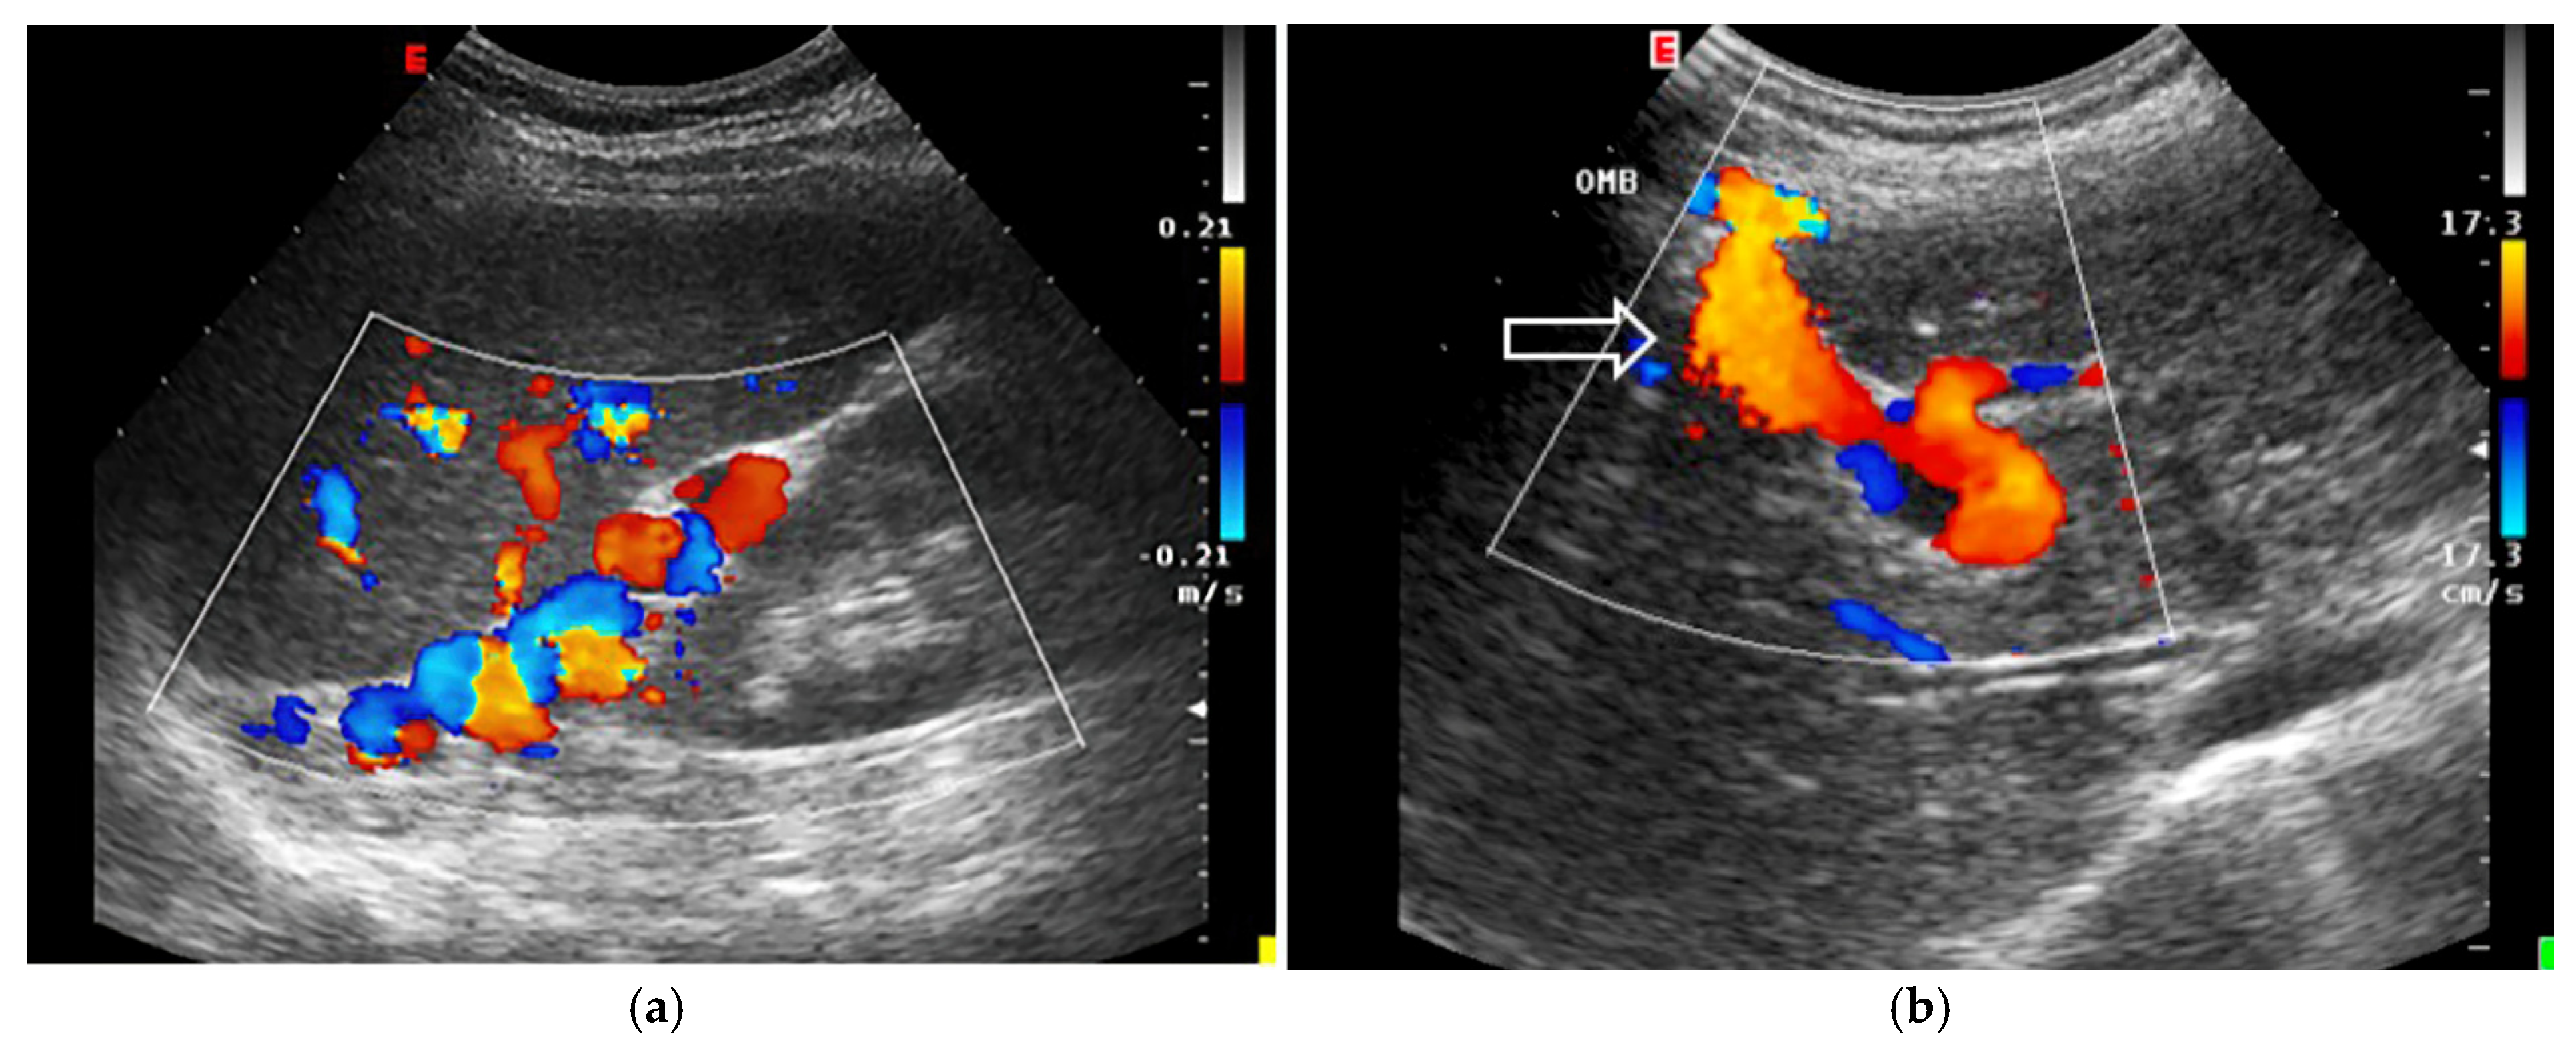

- Increased Pulsatility (Pulsatile Waveform): A pulsatile portal venous flow occurs when there is a significant difference between peak systolic and end-diastolic velocities. This is due to abnormal transmission of pressure through the hepatic sinusoids, often caused by conditions like tricuspid regurgitation, right-sided heart failure (CHF), or arteriovenous shunting (as seen in cirrhosis or hereditary haemorrhagic telangiectasia (Figure 9A) [105]. Pulsatility can be differentiated clinically, with right-sided CHF and tricuspid regurgitation identifiable through the hepatic venous waveform and grayscale US showing dilated hepatic veins, unlike in cirrhosis, where hepatic veins are compressed.

- Slow Portal Venous Flow: Slow flow occurs when back pressure restricts forward flow, typically indicating portal hypertension. In these cases, peak velocity is less than 16 cm/s [106]. Causes of portal hypertension include cirrhosis, portal vein thrombosis (prehepatic), and right-sided heart failure (posthepatic). The most specific findings include the development of portosystemic shunts (like a recanalized umbilical vein) and slow or reversed (hepatofugal) flow.

- Hepatofugal (Retrograde) Flow: Hepatofugal flow happens when the pressure in the portal vein exceeds that of the liver, causing flow to reverse and appear below the baseline. This is another indicator of portal hypertension, which can be caused by various conditions, including cirrhosis, right-sided heart failure and other portal vein obstructions [107] (Figure 9).Figure 9. (A) Increased pulsatility due to arteriovenous shunting in a case of hereditary haemorrhagic telangiectasia; (B) Reduced Portal Flow in a case of cirrhosis (C) Hepatofugal Flow of Portal Vein is a late sign of Portal Hypertension. It happens when the pressure in the portal vein exceeds that of the liver, causing flow to reverse and appear below the baseline. This is another indicator of portal hypertension, which can be caused by various conditions, including cirrhosis, right-sided heart failure and other portal vein obstructions.Figure 9. (A) Increased pulsatility due to arteriovenous shunting in a case of hereditary haemorrhagic telangiectasia; (B) Reduced Portal Flow in a case of cirrhosis (C) Hepatofugal Flow of Portal Vein is a late sign of Portal Hypertension. It happens when the pressure in the portal vein exceeds that of the liver, causing flow to reverse and appear below the baseline. This is another indicator of portal hypertension, which can be caused by various conditions, including cirrhosis, right-sided heart failure and other portal vein obstructions.